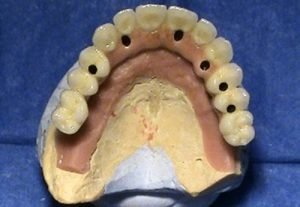

Prosthetic treatment in a toothless jawbone carried - 4 implants

Implantation solution of the posterior toothless sections in the jaw